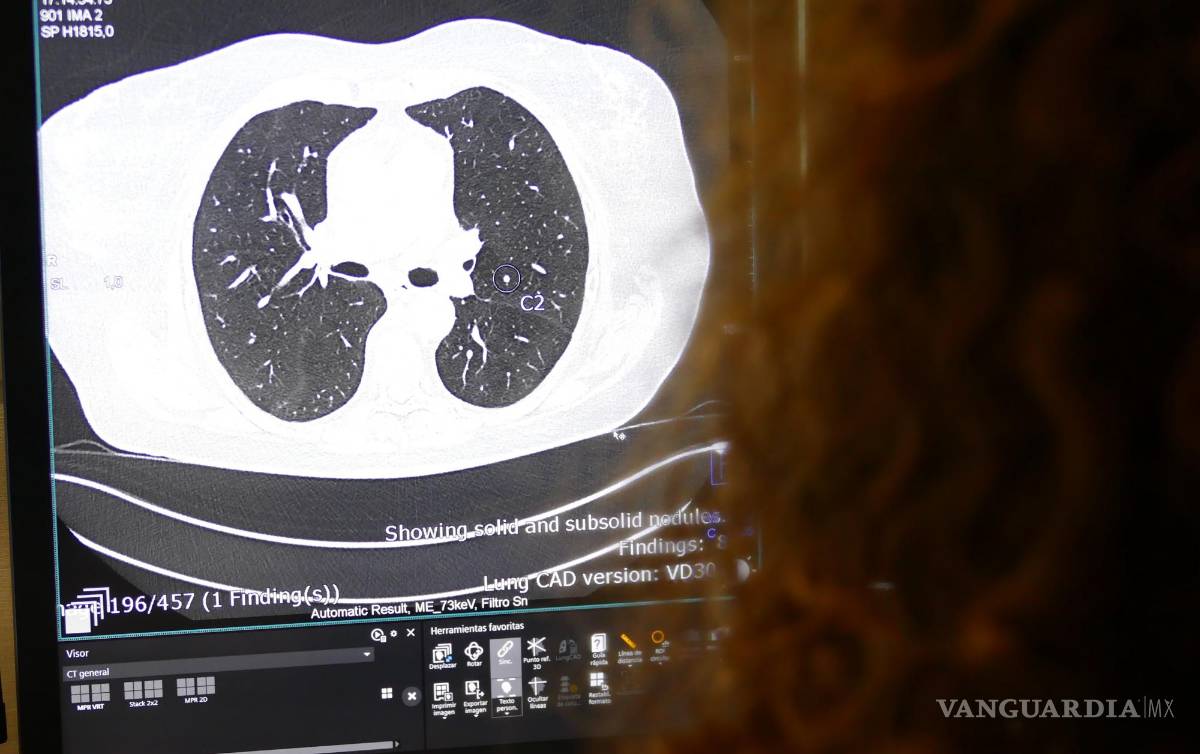

$!Imagen de una tomografía computarizada pulmonar en la que la IA muestra la presencia de un nódulo pulmonar sospechoso.

Este especialista también destaca las herramientas de IA utilizadas en las nuevas tecnologías de Diagnóstico por la Imagen, como la tomografía computarizada Photon Counting, que “posibilitan efectuar análisis instantáneos de presencia de nódulos pulmonares o derrames cerebrales”.

Este escáner detecta automáticamente los nódulos pulmonares. Si observa su presencia envía la prueba marcada al radiólogo que debe confirmar su presencia. Lo mismo hace con las tomografías computarizadas cerebrales; si detecta una hemorragia, alerta a los especialistas”, señala Martínez de Vega.

Hasta hace no mucho tiempo un escáner de tórax estaba compuesto por 50 imágenes. Ahora tiene 1,200. Ningún radiólogo puede analizar tantas imágenes. Necesitamos que la IA nos ayude. Además, hay lesiones que el ojo humano no ve y que la IA detecta”, explica.